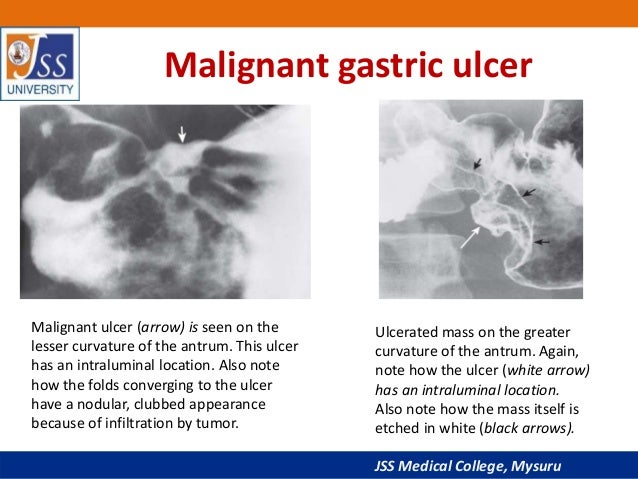

Gastric cardia radiology. Diagnostic centers of america dca is a leading diagnostic imaging facility offering a full array of imaging services in palm beach county florida. We have five state of the art radiology imaging centers in boca raton boynton beach delray beach and wellington florida. The gastric cardia is characterized on barium stud ies by three or four stellate folds that radiate to a central point at the gastro esophageal junction also known as the cardiac rosette fig 2 12. Variations and benign influences may closely resemble the more dangerous lesion.

A healthier weight from surgery can help improve or resolve many obesity related conditions such as type 2 diabetes high blood pressure joint pain heart disease and more. Medically treated small gastric ulcer. Left and right gastric veins drain to portal vein. Ugis has a 70 90 detection rate.